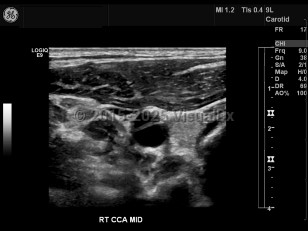

Imaging Studies image of Carotid artery dissection - imageId=7872495. Click to open in gallery.  caption: '<span>Common carotid artery dissection.   Grayscale ultrasound image demonstrates a luminal flap within the common  carotid artery. Dissection was confirmed by CT angiogram (not shown).</span>'

Common carotid artery dissection. Grayscale ultrasound image demonstrates a luminal flap within the common carotid artery. Dissection was confirmed by CT angiogram (not shown).